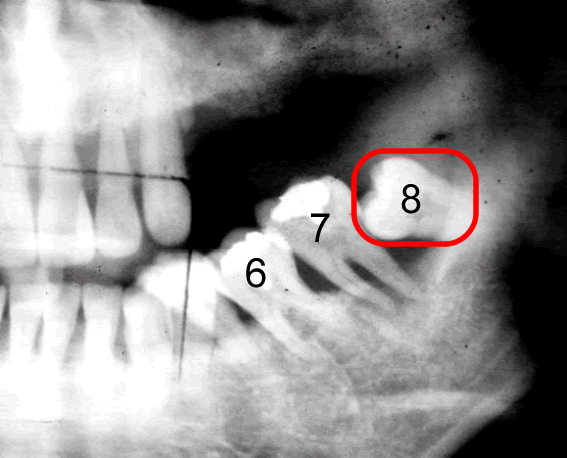

さて次のレントゲンをご覧下さい。

親知らずの手前の7番目の歯、上に飛び出てますよね。

グイグイグイと「どけどけどけ!」と。

いまだにこの「親知らず」活発です。

このままほっといても7番目は抜けてしまいます。

「親知らず」が原因で7番目の歯が勝手に抜けちゃうわけです。

飛び出て行っちゃいます。

8番目と7番目、歯というのは頭があり根っこがあるんですけれども、頭でっかちなんです。

7 番目の首根っこのへっこんだところに8番目の歯が突っ込んできたらどうなるでしょう。

頭でっかちが7番目の頭でっかちの下に潜り込むような形になってきます。

ですので、このままじっとしておいてくれたらいのですが、ところが親知らずは出たがりです。

手前の歯が引っかかったままグイグイグイと押し上げます。

そうすると7番目6番目が噛み合わせの位置がだんだんと飛び出てくるわけです。